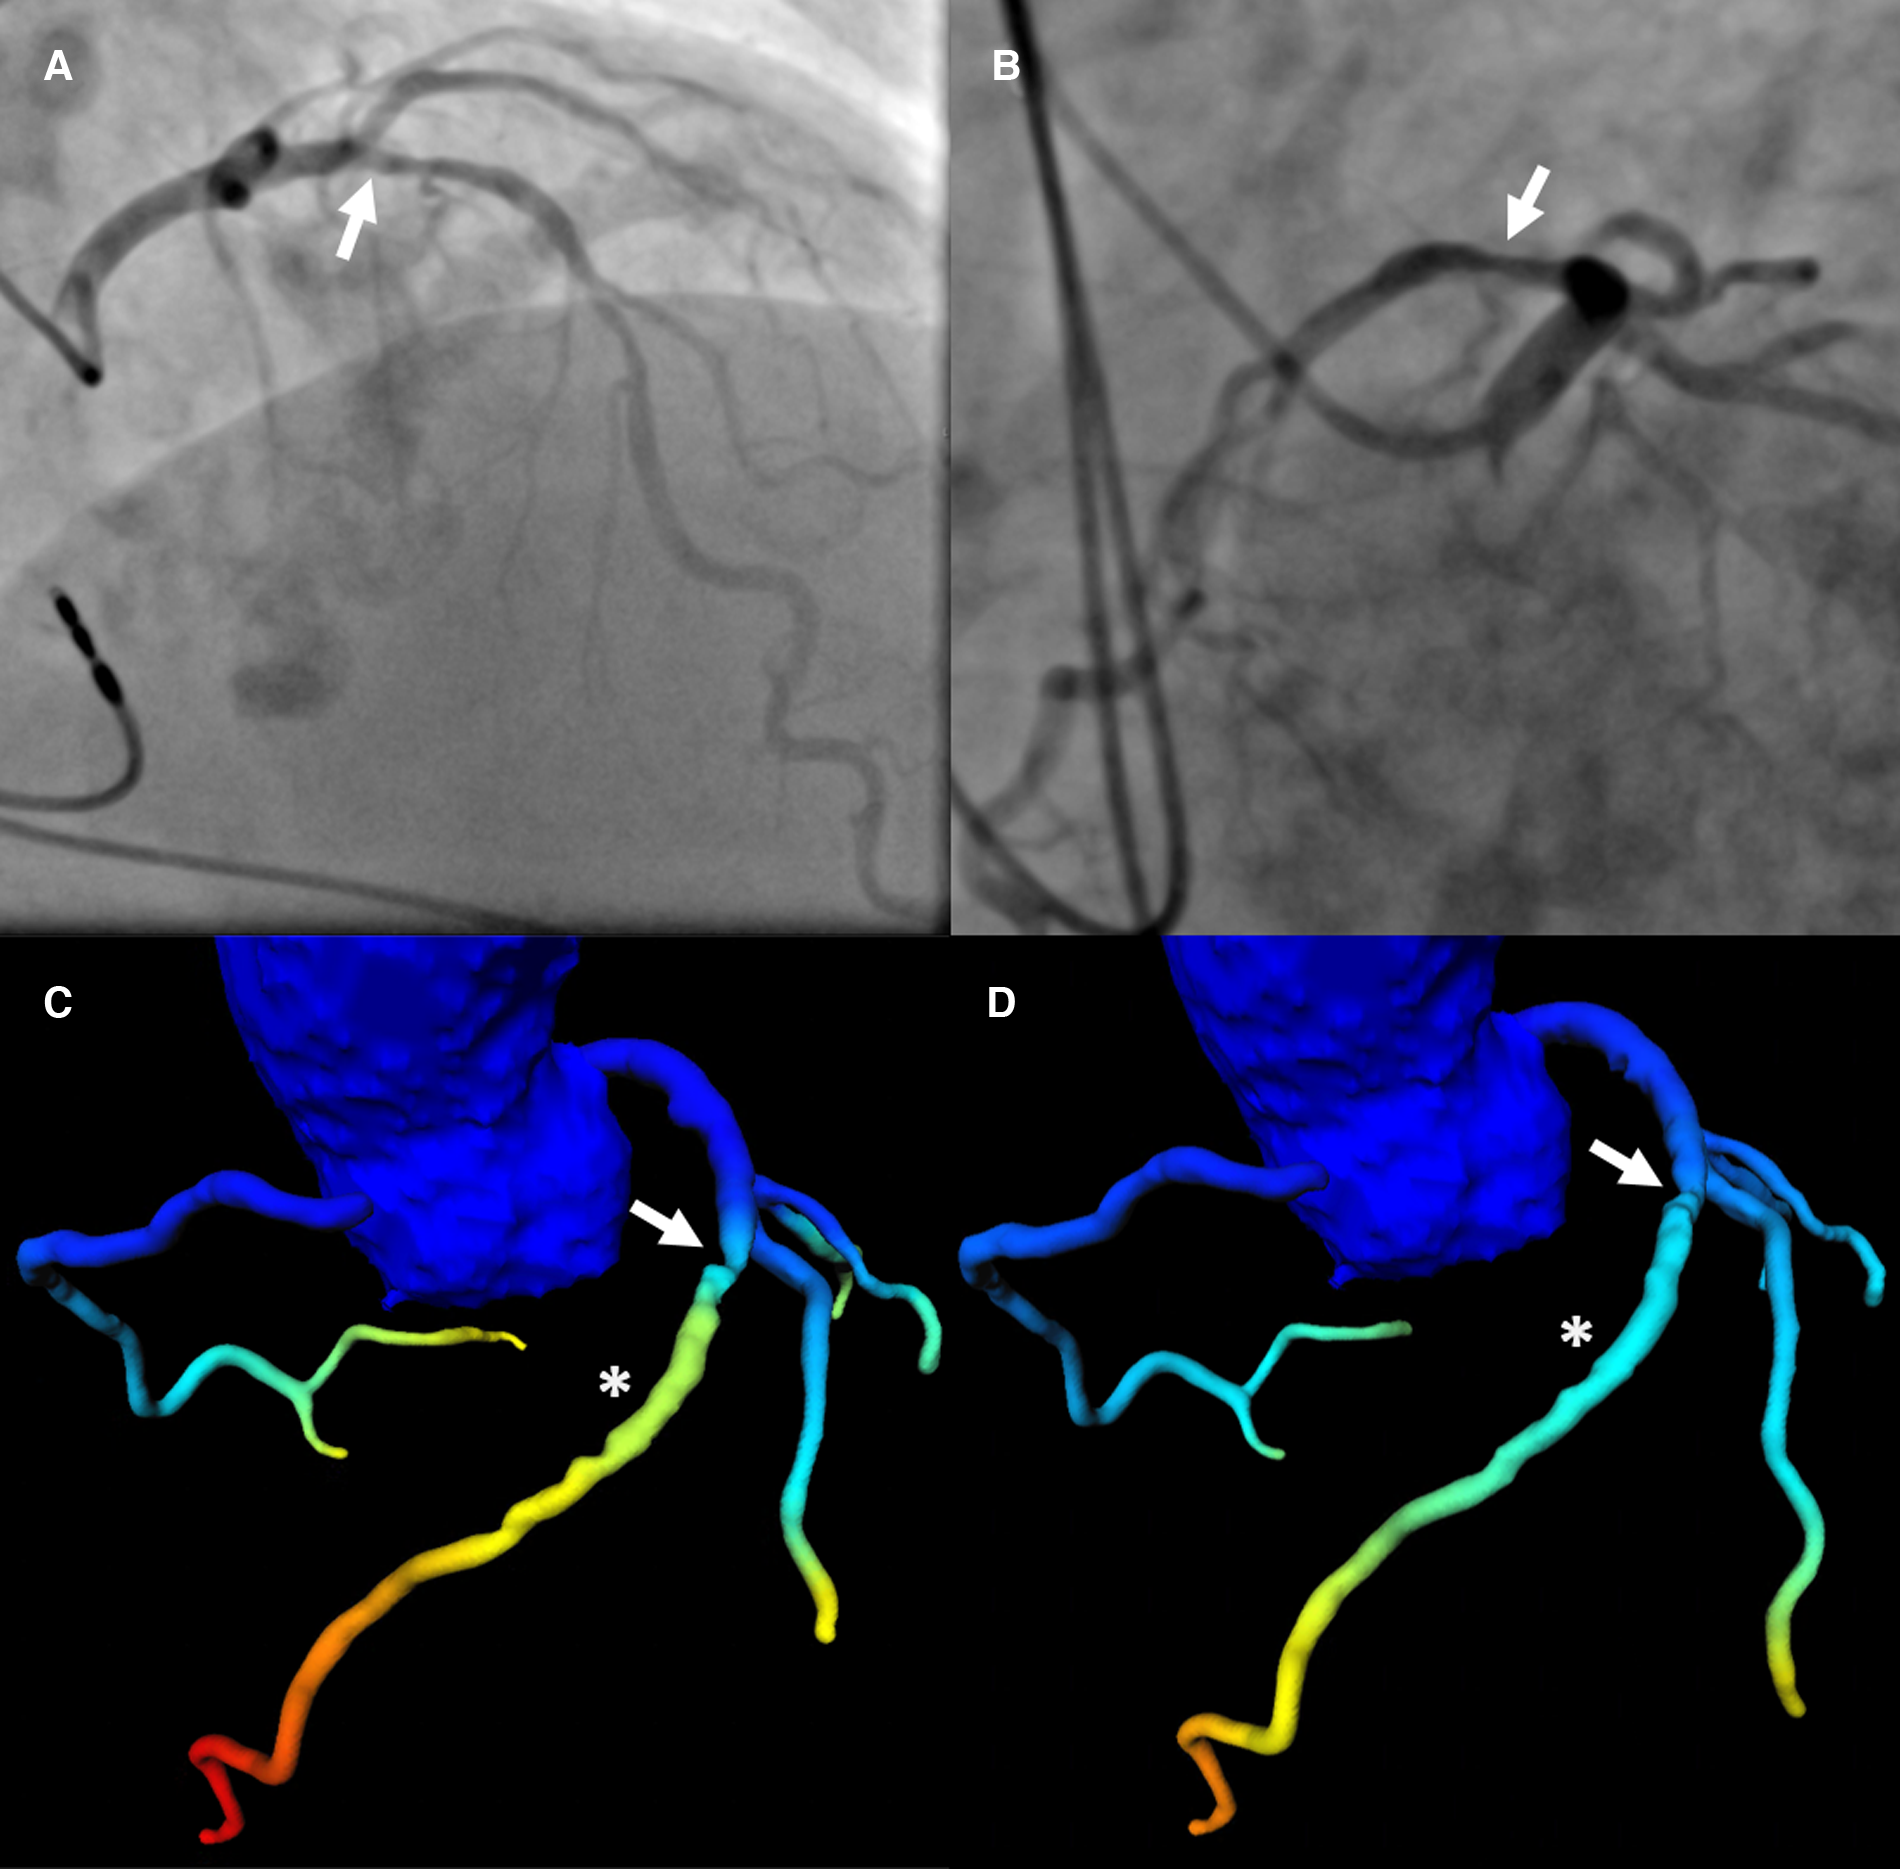

Figure 4

Patient with severe LAD stenosis and discrepant categorization according to CT-FFR values. Patient with severe stenosis (arrow in a-d) in the middle LAD (S7) on ICA (QCA: 78%) (A,B) and results of CT-FFR of observer A (C) and observer B (D) CT-FFR values were taken approximately 2 cm distal to the stenosis (asterisk in C,D). The CT-FFR value measured by observer A was 0.79, indicating hemodynamically significant CAD (C), the value measured by observer B was 0.86, indicating non-significant CAD (D) The threshold for hemodynamically significant CAD was ≤0.80. CAD, coronary artery disease; CT-FFR, CT-derived fractional flow reserve; ICA, invasive coronary angiography; LAD, left anterior descending artery; QCA, quantitative coronary analysis.

Patients prior to TAVR assessed with ML-based CT-FFR by two observers with differing experience were sometimes categorized differently into having hemodynamically relevant CAD or not. This was independent of image quality or CAC. This can easily be understood if values fall close to the cut-off and CT-FFR is only measured at a single point in a fixed distance distal to the stenoses (Figure 4). However, hemodynamical implications of luminal narrowing can manifest distal to that point of measurement (21). On the other hand, diffuse arteriosclerosis without a distinct stenosis may have a cumulative effect (41) additive to or independent of the stenosis measured. Instead of a single measurement with a fixed cut-off, a relative decrease of CT-FFR values along the coronary tree could perhaps prove more representative for the global hemodynamic situation (21, 41–44) of the coronary arterial vasculature.